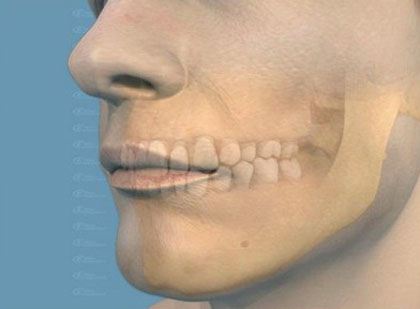

Каждый зуб взрослого человека состоит из коронки, шейки и корня. Коронка находится непосредственно над десной. Суженная часть - шейка - расположена в десне и охватывается ею. Корень находится в альвеоле.

На верхушке корня расположено отверстие, через которое проходят сосуды и нервы. Внутри коронки зуб человека имеет две полости: широкую-с коронковым отделом и суживающуюся – с корневым отделом. Суживающаяся часть полости называется корневым каналом.

Полость зуба заполнена насыщенной нервами и сосудами зубной мякотью. Корни зубов, посредством альвеолярной надкостницы, плотно сращены с поверхностями ячеек зубов. Надкостница включает множество кровеносных сосудов. В состав твердого вещества зуба входят: эмаль; дентин;цемент.

Вещество, составляющее основную массу зуба - дентин. Снаружи коронка покрыта эмалью, а корень - цементом.

Стенка альвеолы, периодонт, десна и сам зуб вместе составляют зубной орган. Все зубы имеют схожее строение. Коронки зубов расположены в две зубные дуги: верхний и нижний зубные ряды, в каждом из них по 14-16 зубов.